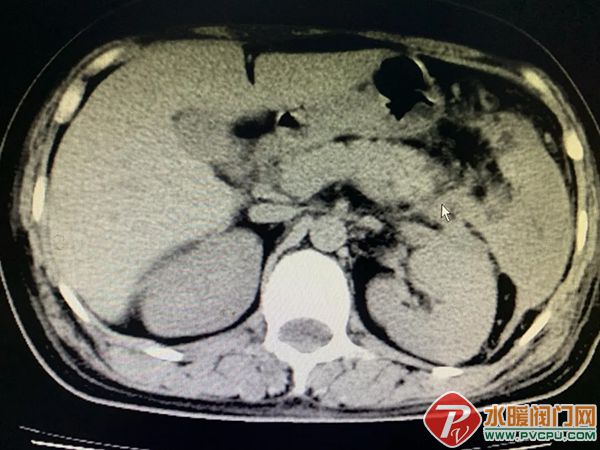

近日,患者洪某某,因持续腹痛5天,在外院初步诊断为肠梗阻,为求进一步治疗转诊至仑苍镇卫生院。 接诊后,仑苍镇卫生院医生高度重视,迅速为患者展开细致检查。当抽血结果显示血淀粉酶显著升高,结合腹部CT影像学表现,医务人员凭借扎实的临床经验,敏锐地鉴别:并非单纯性肠梗阻,而是急性胰腺炎继发的麻痹性肠梗阻! 急性胰腺炎起病急、进展快、病情凶险,早期精准识别是救治关键。此次及时鉴别为后续规范救治争取了宝贵时间。 为确保患者得到专业救治,仑苍镇卫生院迅速启动救治流程,第一时间对接南安市医院消化内科庄宇亮副主任医师。在庄主任的悉心指导下,仑苍镇卫生院医护团队快速为患者制定个体化综合治疗方案,及时开展胃肠减压、导泻、抑酶、补液等规范治疗,全程密切监测患者生命体征,根据病情变化及时调整诊疗方案,全力保障救治效果。 经庄主任及仑苍镇卫生院医护人员精心诊疗、细致护理,患者病情得到快速控制,腹痛症状显著缓解,生命体征平稳,各项指标逐步恢复正常。经数日规范治疗,患者痊愈出院。 出院那一刻,她紧紧握住医护人员的手,由衷感谢:“没想到在卫生院也能得到这么专业的治疗,有你们在,我心里踏实多了。”朴实的话语,道出了最真挚的感动。 此次急性胰腺炎患者的成功救治,正是仑苍镇卫生院践行医者使命、守护群众健康的真实写照。一直以来,仑苍镇卫生院始终坚持“以患者为中心”,不断加强学科建设,提升诊疗技术水平,持续强化急危重症救治能力。我们深知,每一次能力的提升,努力让群众在家门口就能享受到安全、优质的医疗服务。 未来,仑苍镇卫生院将继续坚守医者初心,以更精湛的技术、更温暖的服务,全力守护全镇人民的生命健康,做百姓信得过、靠得住的健康守门人!